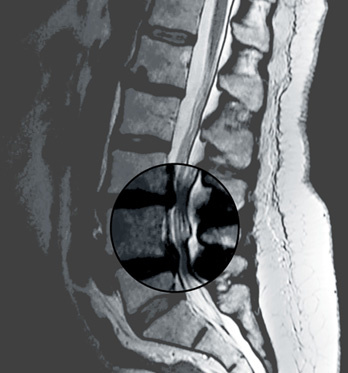

Das Kernspintomogramm (MRI) zeigt eine Verengung des Wirbelkanals mit Einklemmung der Spinalnerven auf zwei Höhen.